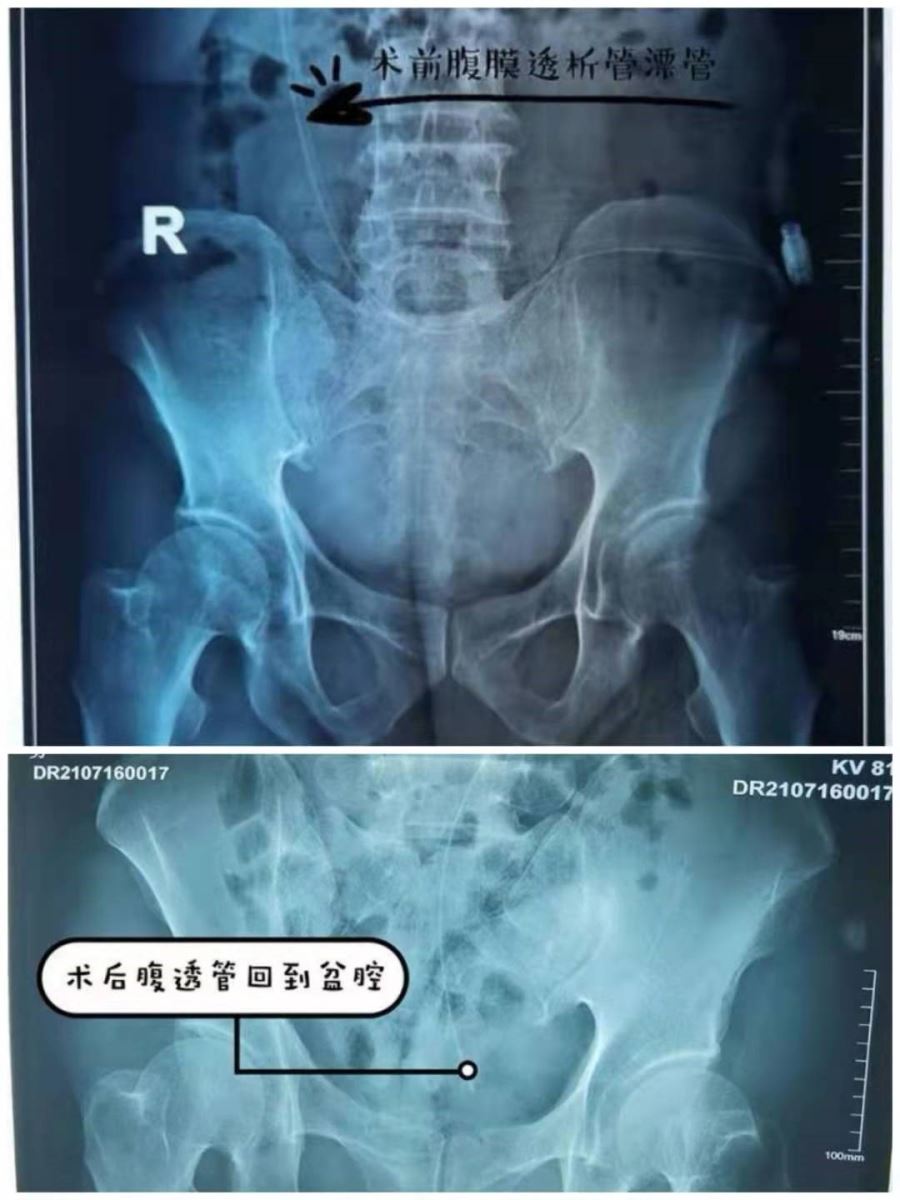

患者张某,规律腹膜透析半年,导管功能不良入院,经腹部正侧位 X 线片检查证实导管移位,通过积极常规重力复位、手法复位、导泻法等方法尝试后,X线片证实导管仍移位,且仍存在导管引流障碍,经过王立娜主管医生与患者的充分沟通、积极准备,肾病风湿免疫科高丽主任决定为该患者行腹膜透析管导丝法复位术,此项治疗成功率较高,无需给予患者进行麻醉,可保留原腹透管,并可以在非 X 线直视下进行,减少放射性接触,导丝复位不增加患者创伤,并且费用少。但手术难度高,风险大,对操作医生有较高要求,非常考验医生的技术水平。最终,王连庭医生凭借精湛的医术,顺利完成手术,术后即刻可见液体呈线样流出,腹膜透析液引出良好,行 X 线片检查提示腹透管位置正常,术后随访患者腹膜透析引流通畅。